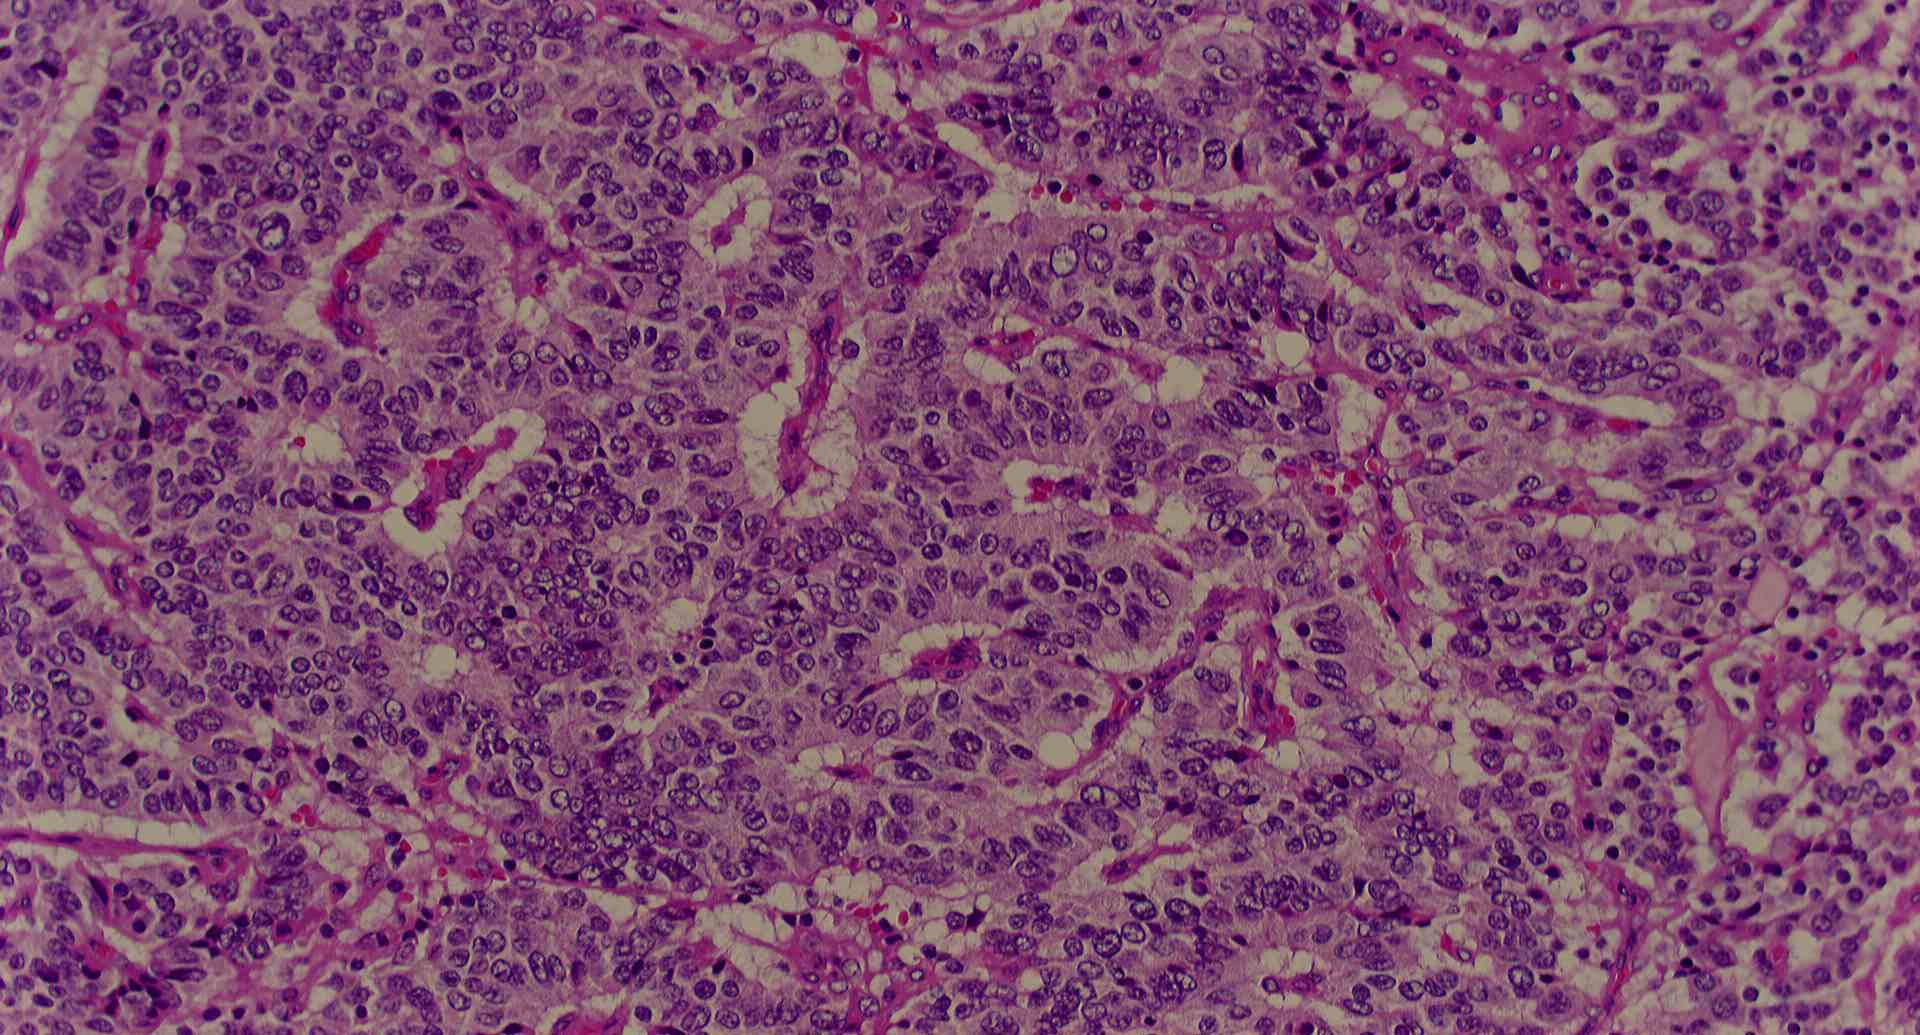

標本17